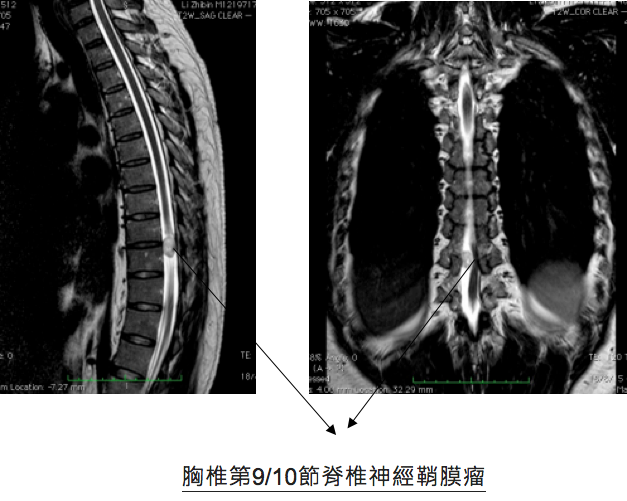

48歲李先生從國內到香港找醫生醫治他的雙腿痳痺及乏力症狀,他已在國內兩年間接受中西療法都不能把他的症狀改善。李先生兩年前只覺得腳踭痛,但慢慢發現腳步走路不穩及大腿肌肉無力,同時漸漸雙腿有痳痺感覺,快步時有困難提腿。近期還影響了小便有頻密現象。經詳細問診及驗查後,發現李生的症狀實在太不尋常,可能是嚴重椎間盤突出壓著馬尾神經引起馬尾神經綜合症(Cauda Equina Syndrome ),又或是脊椎腫瘤壓著脊髓影響病變。筆者立刻安排磁力共振掃描脊椎,果然發現胸椎第9/10節脊椎裡面長了一個2cm大的神經鞘膜瘤( Nerve Sheath Spinal Tumor)已嚴重地壓著脊髓。當日立刻轉介到腦神經外科醫生安排入院作手術切除腫瘤 。術後第二天病人已感覺雙腳乏力及痳痺大大改善了。

脊椎神經鞘膜瘤

脊椎管腔內良性腫瘤不會轉移到其他部位,也不會有立即性生命危害,但因生長在脊椎管腔內,體積大時會壓迫脊髓神經,產生類似坐骨神經痛的症狀,嚴重時會導致下半身癱瘓,久而久之將無法恢復正常。